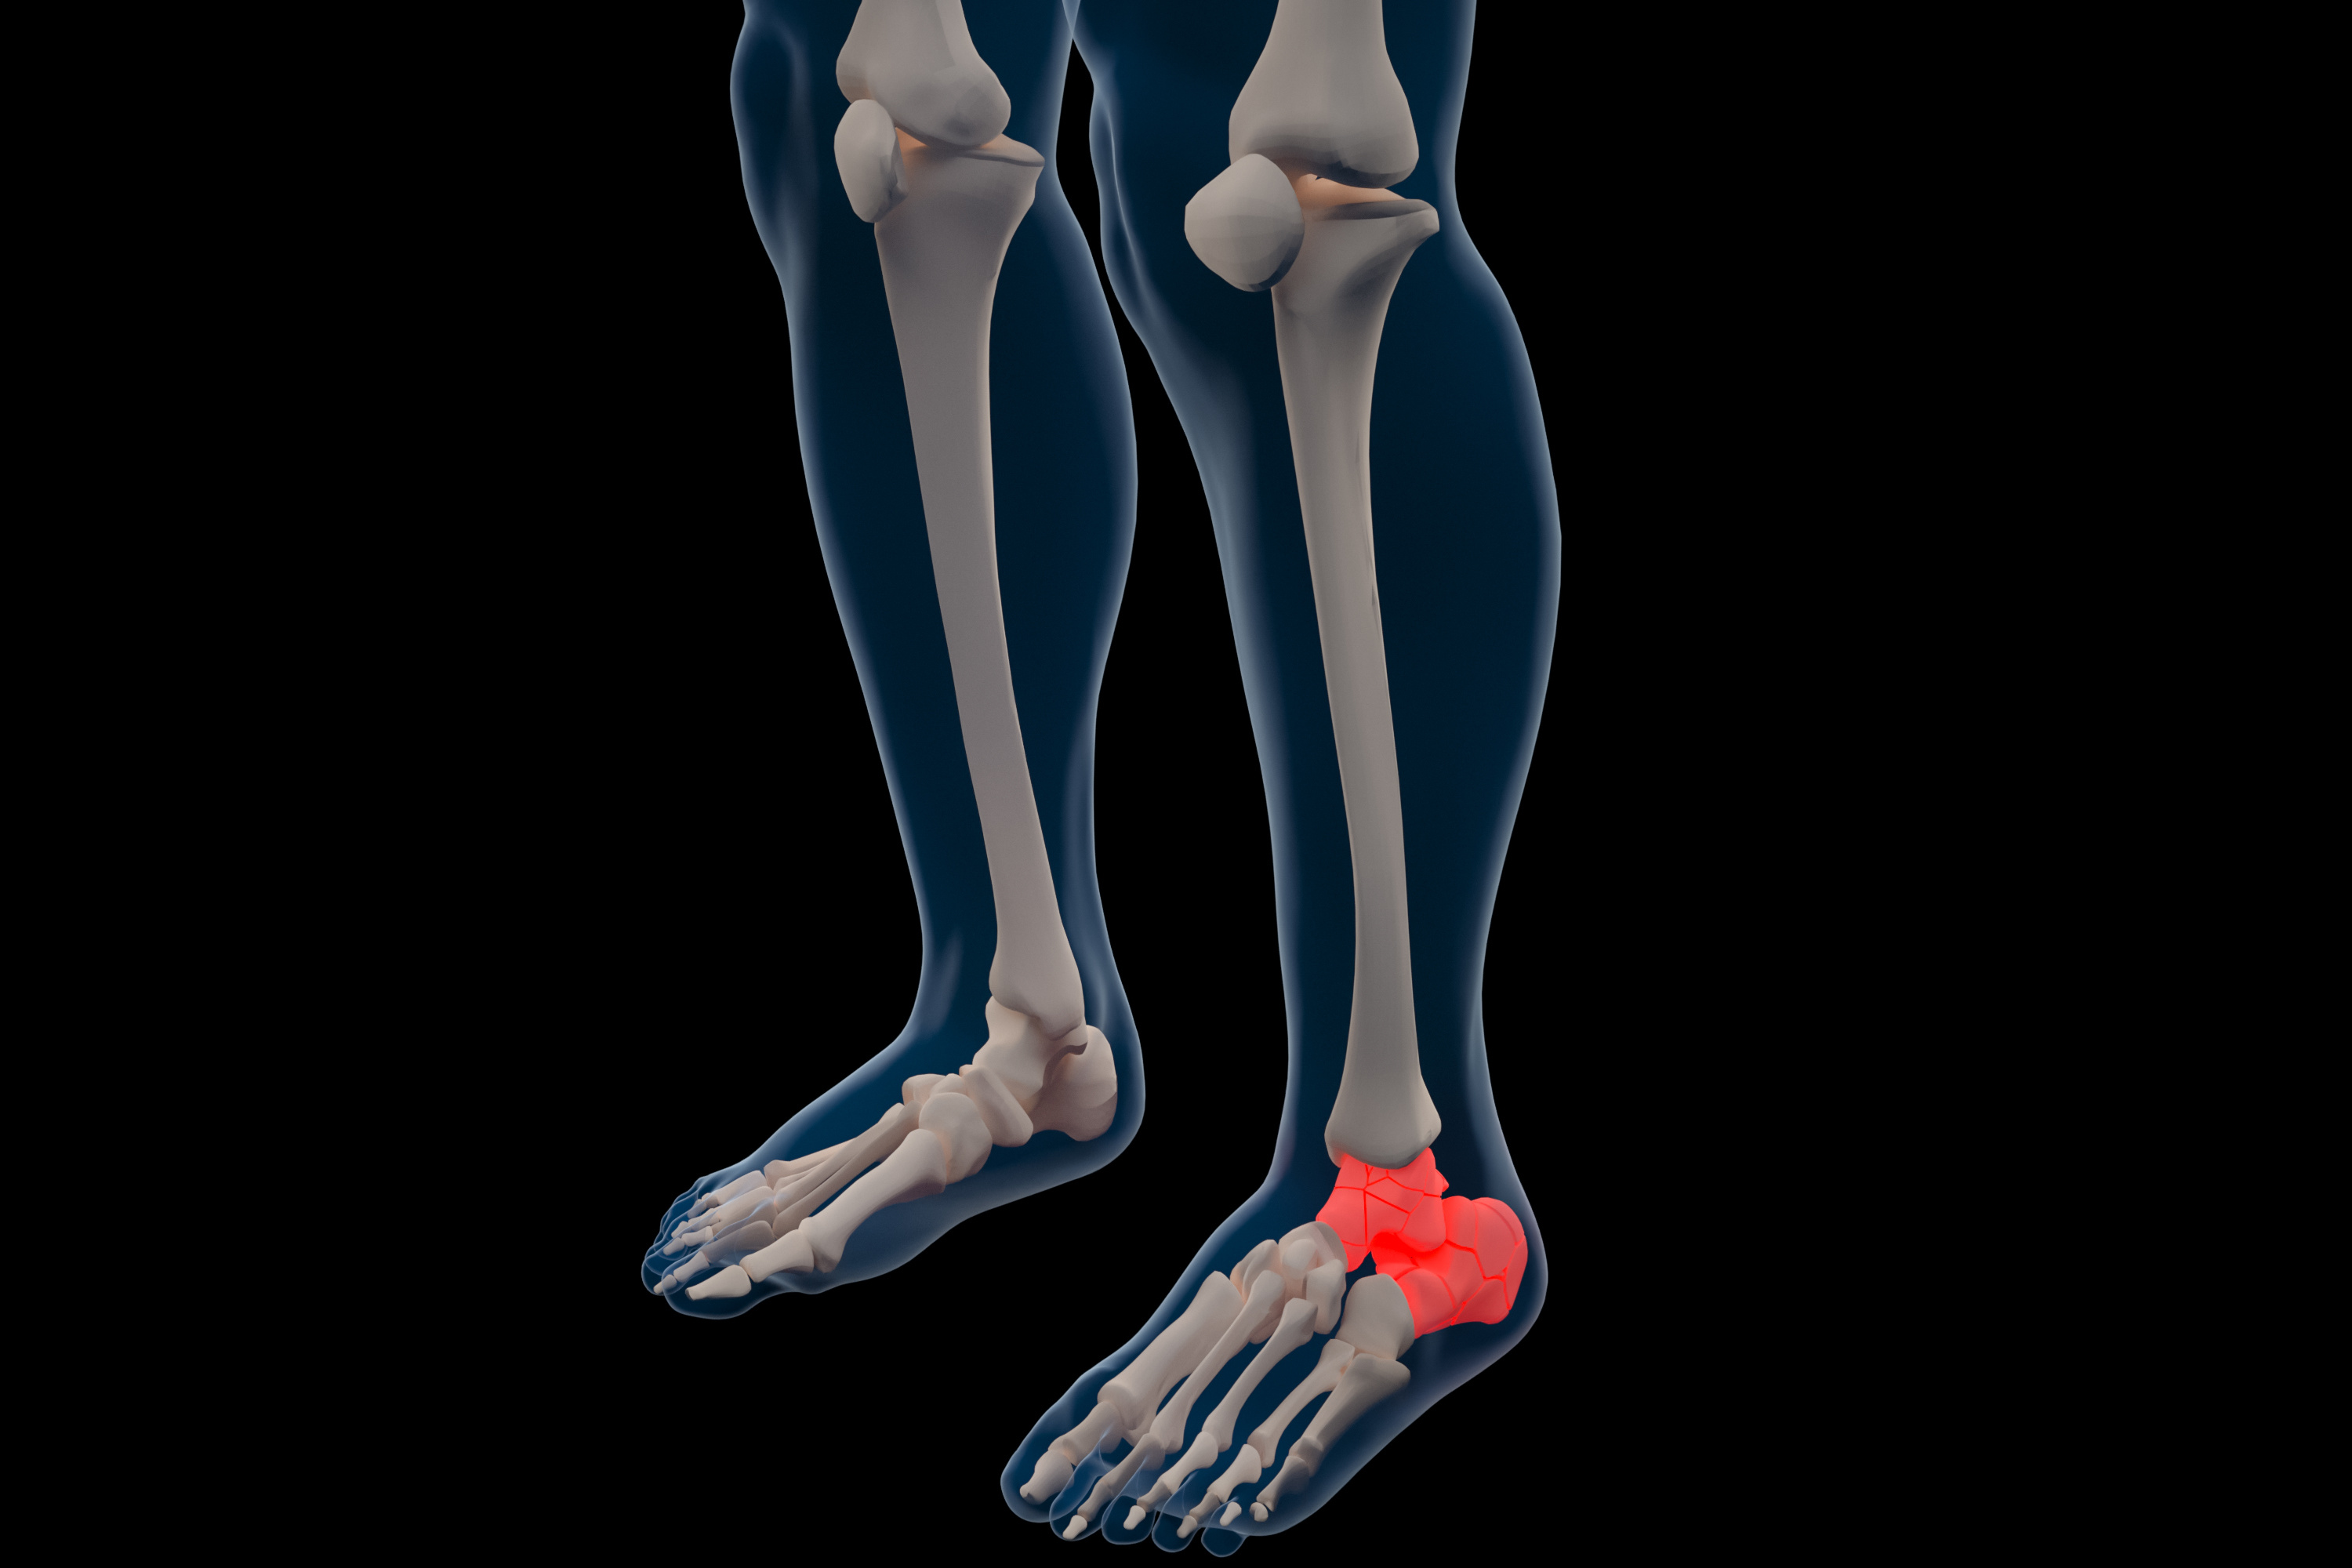

干货:德国医生跟骨骨折手术治疗技巧分享!